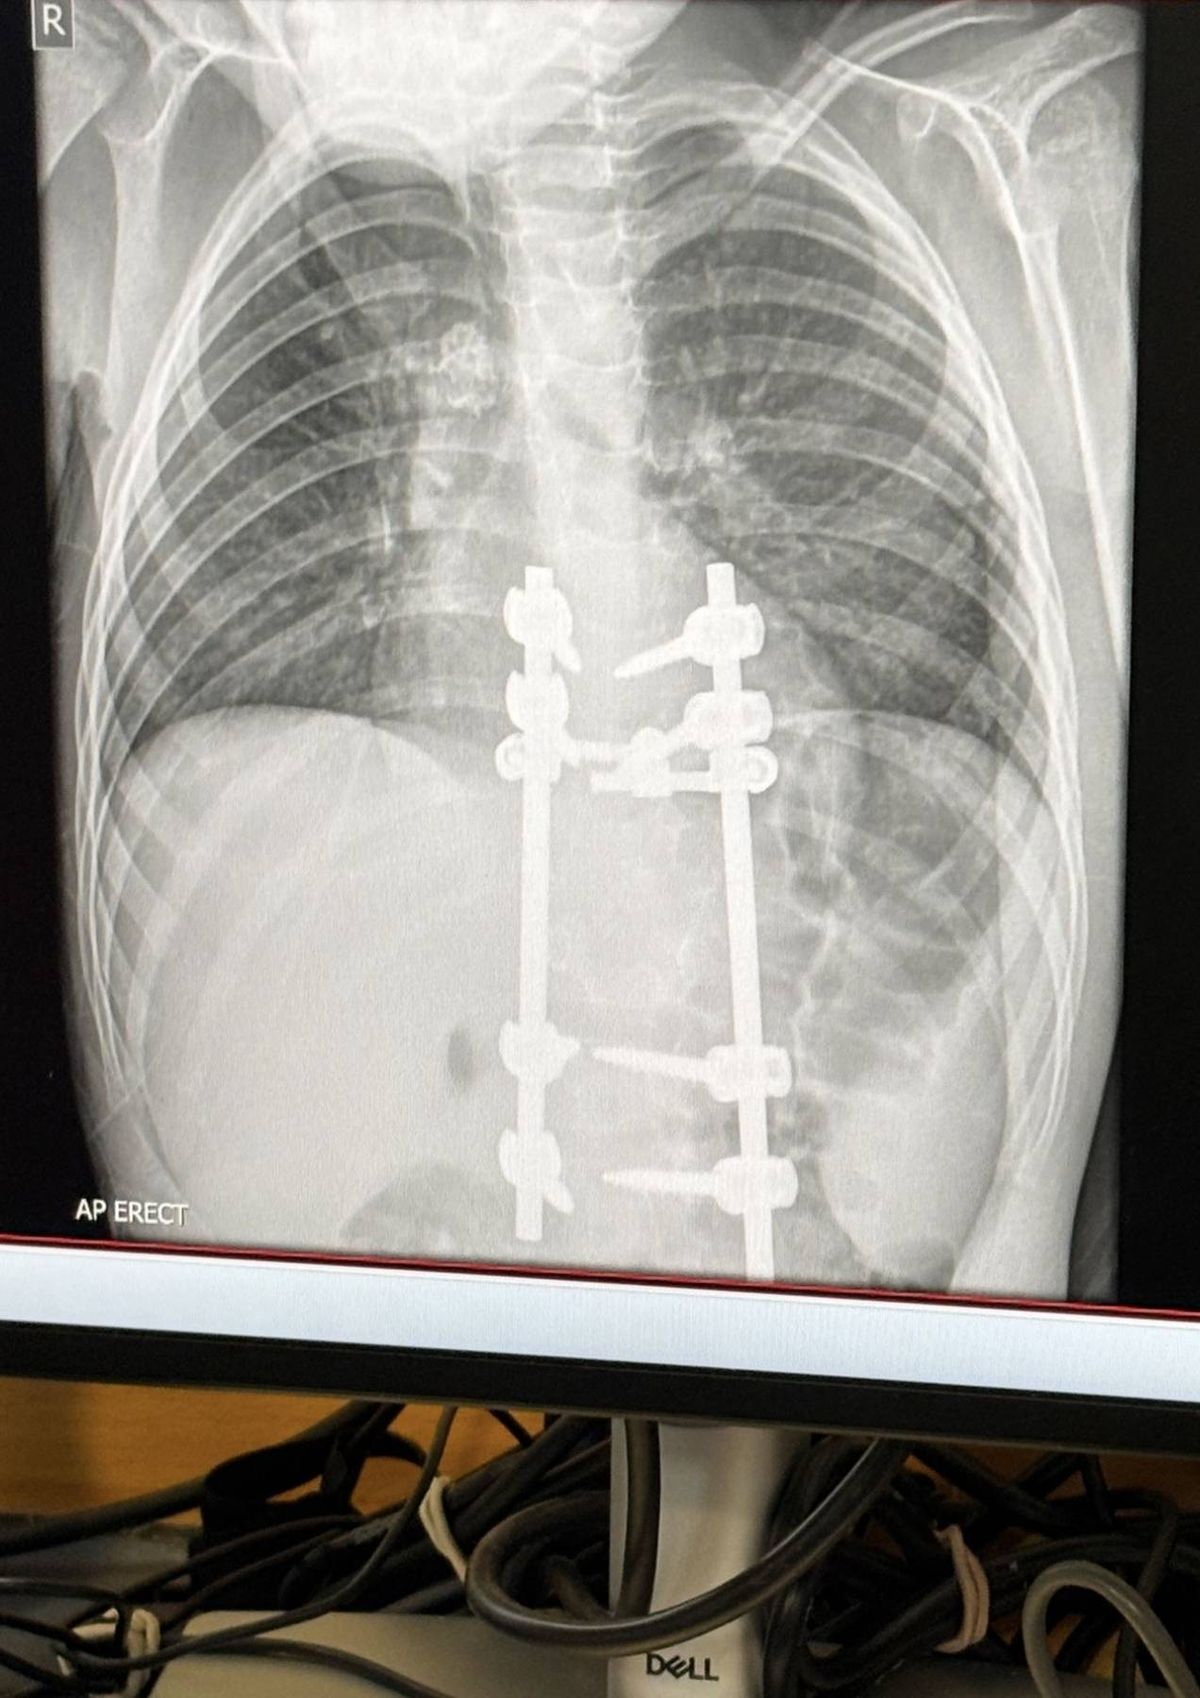

Yet an X-ray conducted in June 2025 uncovered that the youngster was actually battling spinal tuberculosis – a bacterial condition that can impact the vertebrae.

“He would say ‘my legs don’t work’, we went to A&E and did the x-ray and that’s how we found he had tuberculosis.

“The X-ray showed calcified lymph nodes in his lungs and they recognised the TB, it means there was a previous infection in his lungs.

An X-ray revealed the truth(Image: Kennedy News and Media)